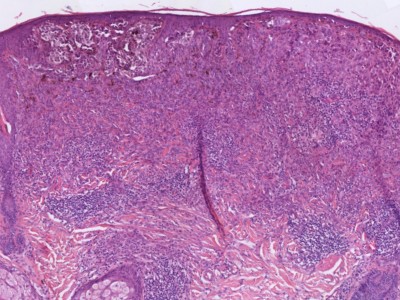

PA:Ook histologisch is het

superficial

spreading melanoom de meest voorkomende variant. Hierbij zijn de nesten van

atypische melanocyten gelegen in een band onder de epidermis. Er is

hoofdzakelijk groei in horizontale richting. Soms is er plaatselijk een

verticale groeifase, met invasie in de diepte of juist exofytische groei

zoals bij een

nodulair melanoom. Een andere veel voorkomende variant is het

in-situ melanoom, dat klinisch meestal beschreven wordt als lentigo maligna.

Kenmerken van maligniteit zijn melanocyten die opstijgen in de epidermis

(ascensie) of de dermis ingroeien, maar ook cellulaire kenmerken van de

melanocyten zelf (cytonucleaire atypie, kernpolymorfie, hyperchromatische

kernen, ruim helder tot eosinofiel cytoplasma, mitosefiguren). In het PA

verslag is de diepte van invasie belangrijk. Dit kan worden beschreven

t.o.v. de huidlagen (Clark levels), maar het is gebruikelijk om het te meten

in mm vanaf de epidermis (Breslow-dikte). Verder is het belangrijk of er epidermale ulceratie

is. Andere kenmerken die de patholoog kan beschrijven is (lymf) angio-invasie,

aanwezigheid / aantal dermale mitosefiguren, perineurale groei, lymfocytaire afweer respons, regressie, microsatellitose.